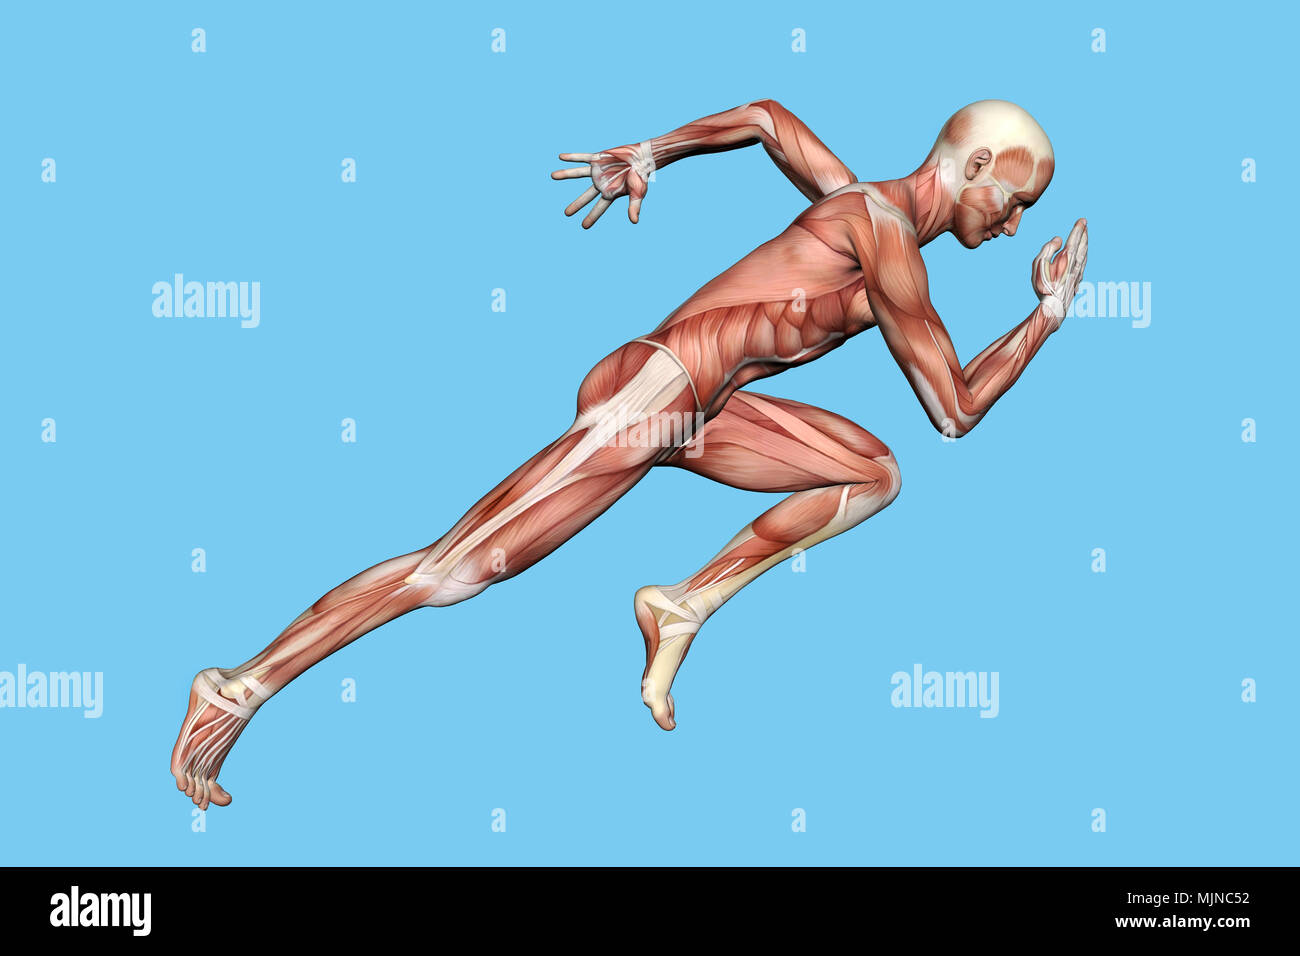

RMFX60TP–Menschen, Anatomie, Muskel, Körper, medizinische, Medizin, Illustration, Mann, Männlich, Gesundheit, muskulös, Wissenschaft, System, Biologie, Muskeln, ich

RF2A9AXYJ–Menschliche Körper Anatomie Muskeln Aufbau eines männlichen, Vorderansicht Seitenansicht und Perspektive, 3D-Rendering im Hintergrund

RFPKG2Y5–3D-Rendering einer männlichen Anatomie-Figur mit Muskeln Karte isolierten auf weißen Hintergrund